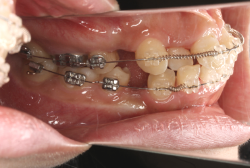

診断の結果、典型的なアングル2級1類の上顎前突です。上下歯列の正中の不一致も見られます。しかし、歯の大きさは平均値に近く、配列の凸凹がそれほど見られません。このまま放置すると、将来的には抜歯を伴う矯正治療を行う可能性が高くなりますが、このタイミングで適切な治療をすると、非抜歯治療が可能かもしれません。

矯正歯科医が着目するのは、奥歯の噛み合わせの位置関係です。前歯の位置にそれなりの差が生じていても、奥歯の位置が正しければそれほど重症という評価にはなりません。このケースの場合は、上下の第一大臼歯の位置関係は、直線的に一致しているタイプでした(矢印が一致)。混合歯列時期の奥歯の位置関係としては、ほぼ正常な状態といえますが、症状から言うと、上の奥歯をもっと後ろに下げてやることができれば、上顎歯列全体に余裕ができるので、凸凹も解消できるし、前歯の傾きを内向きに修正することもできると考えられました。しかしこのまま全体に永久歯が生えきってしまうと、上の前歯が出たままになってしまいますので、生え替わりが完了する前に大急ぎで奥歯を後ろに下げる必要があると判断しました。

こういう症状でもっとも効果があるのが、顎外固定装置と言って、お口の外部から奥歯に力をかける方法です。 写真の装置はネックバンドというタイプの装置です。この装置は取り外し式ですので、夜寝るときに毎日自分で取り付けて、寝ている間に少しずつ上の奥歯を後ろに下げていきます。この装置には、奥歯を後ろに下げる効果だけでなく、上顎の過剰な成長発育の抑制、下顎の成長促進作用があるとされており、上顎前突の症状にはいずれも有利な効果が期待できます。

ネックバンドを1年半使用して、上顎大臼歯が十分後ろに下がったところで、裏側にリンガルアーチという固定のワイヤーを取り付けて、新しく生じた隙間が狭くならないよう「保隙(ほげき)」という処置をして、永久歯が生えそろうまで待機中の様子です。配列全体に隙間が生じているのがお分かりいただけると思います。これだけの隙間が確保できていれば、抜歯をしなくても、あとで上の前歯を内側に理想的な角度で引っ込めることができます。このように完全に永久歯列になる前に、十分な隙間が確保できるかどうかが、非抜歯で矯正できるかどうかの分かれ目になります。

初診時と違い、上の奥歯がより後方に下がっていることが分かります。ただしこの段階では奥歯は後ろに下がりすぎの状態です。しかし次の段階でマルチブラケット法を始めると、上の奥歯は次第に前にズレて来ます。最終段階で正しい位置にするためには、この段階では余分に後ろに下がっている必要があります。